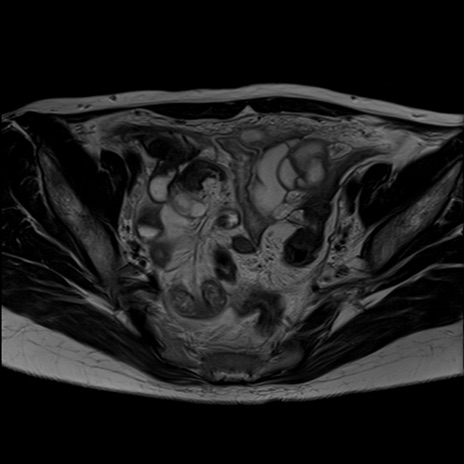

症例39 T2WI(横断像)

MRI(4日後)